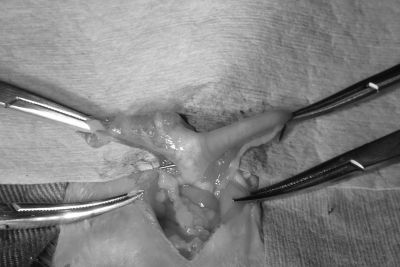

全身麻酔をかけてお腹を開くと、腫れた左の子宮が周りの組織と癒着していました。

子宮と卵巣を摘出し、手術は無事終了しました。